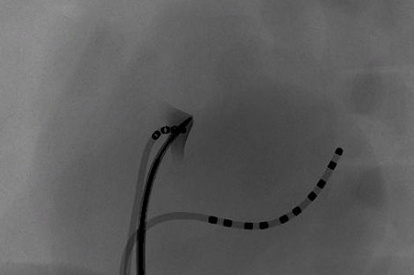

TAVI (Transcatheter Aortic Valve Implantation) Module